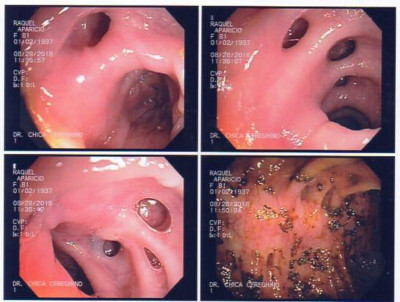

Cálculo gigante por coledocoliatisis